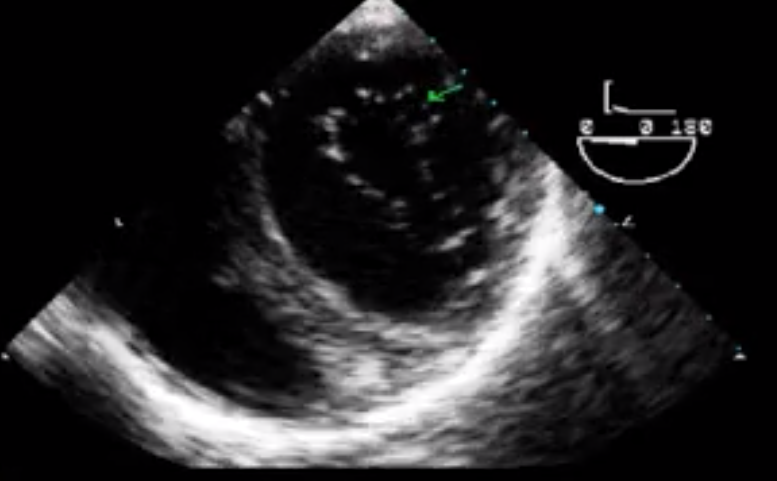

What view is seen here?

Transgastric 2 chamber view

Mitral Valve Subvalvular Apparatus

What walls of the heart are shown here?

INFERIOR = CLOSE TO THE PROBE

ANTERIOR = AWAY FROM THE PROBE

What papillary muscle is seen here?

Posteromedial Papillary Muscle